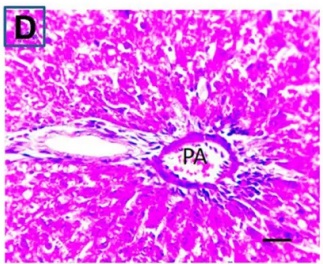

Put the liver tissue section under a microscope, and you can see that cisplatin can cause liver congestion (the blood that should return to the heart is blocked and stagnates in the hepatic veins), cell degeneration (vacuoles appear, which is the earliest change in cellular injury), apoptosis and necrosis, but these conditions can also be alleviated by using Ganoderma lucidum.

Figure 2 Effects of cisplatin and Ganoderma lucidum on hepatocytes